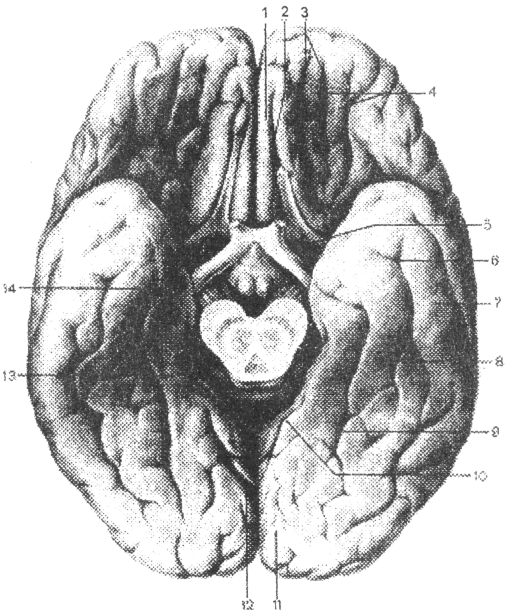

Необычные объекты: Переднее продырявленное вещество